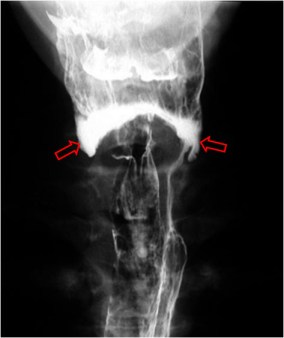

SIGNO DEL ARCO GÓTICO o DE LA TORRE DE AGUJA o DEL RELOJ DE ARENA o DE LA BOTELLA DE VINO

La presencia de edema en la tráquea provoca una pérdida de las convexidades de la tráquea subglótica y, por tanto, de los escalones que forma la columna de aire en la radiografía anteroposterior.

La tráquea subglótica adquiere una forma de «V» invertida o «torre de aguja” (the steeple sign), que también se ha descrito como «arco gótico». También se encuentra en la literatura como Signo del reloj de arena (hourglass sign) o Signo de la botella de vino.

Este signo puede verse tanto en el crup como en la epiglotitis, el edema angioneurótico y la traqueítis bacteriana. Obsérvese la morfología del luminograma laríngeo en este niño con crup.